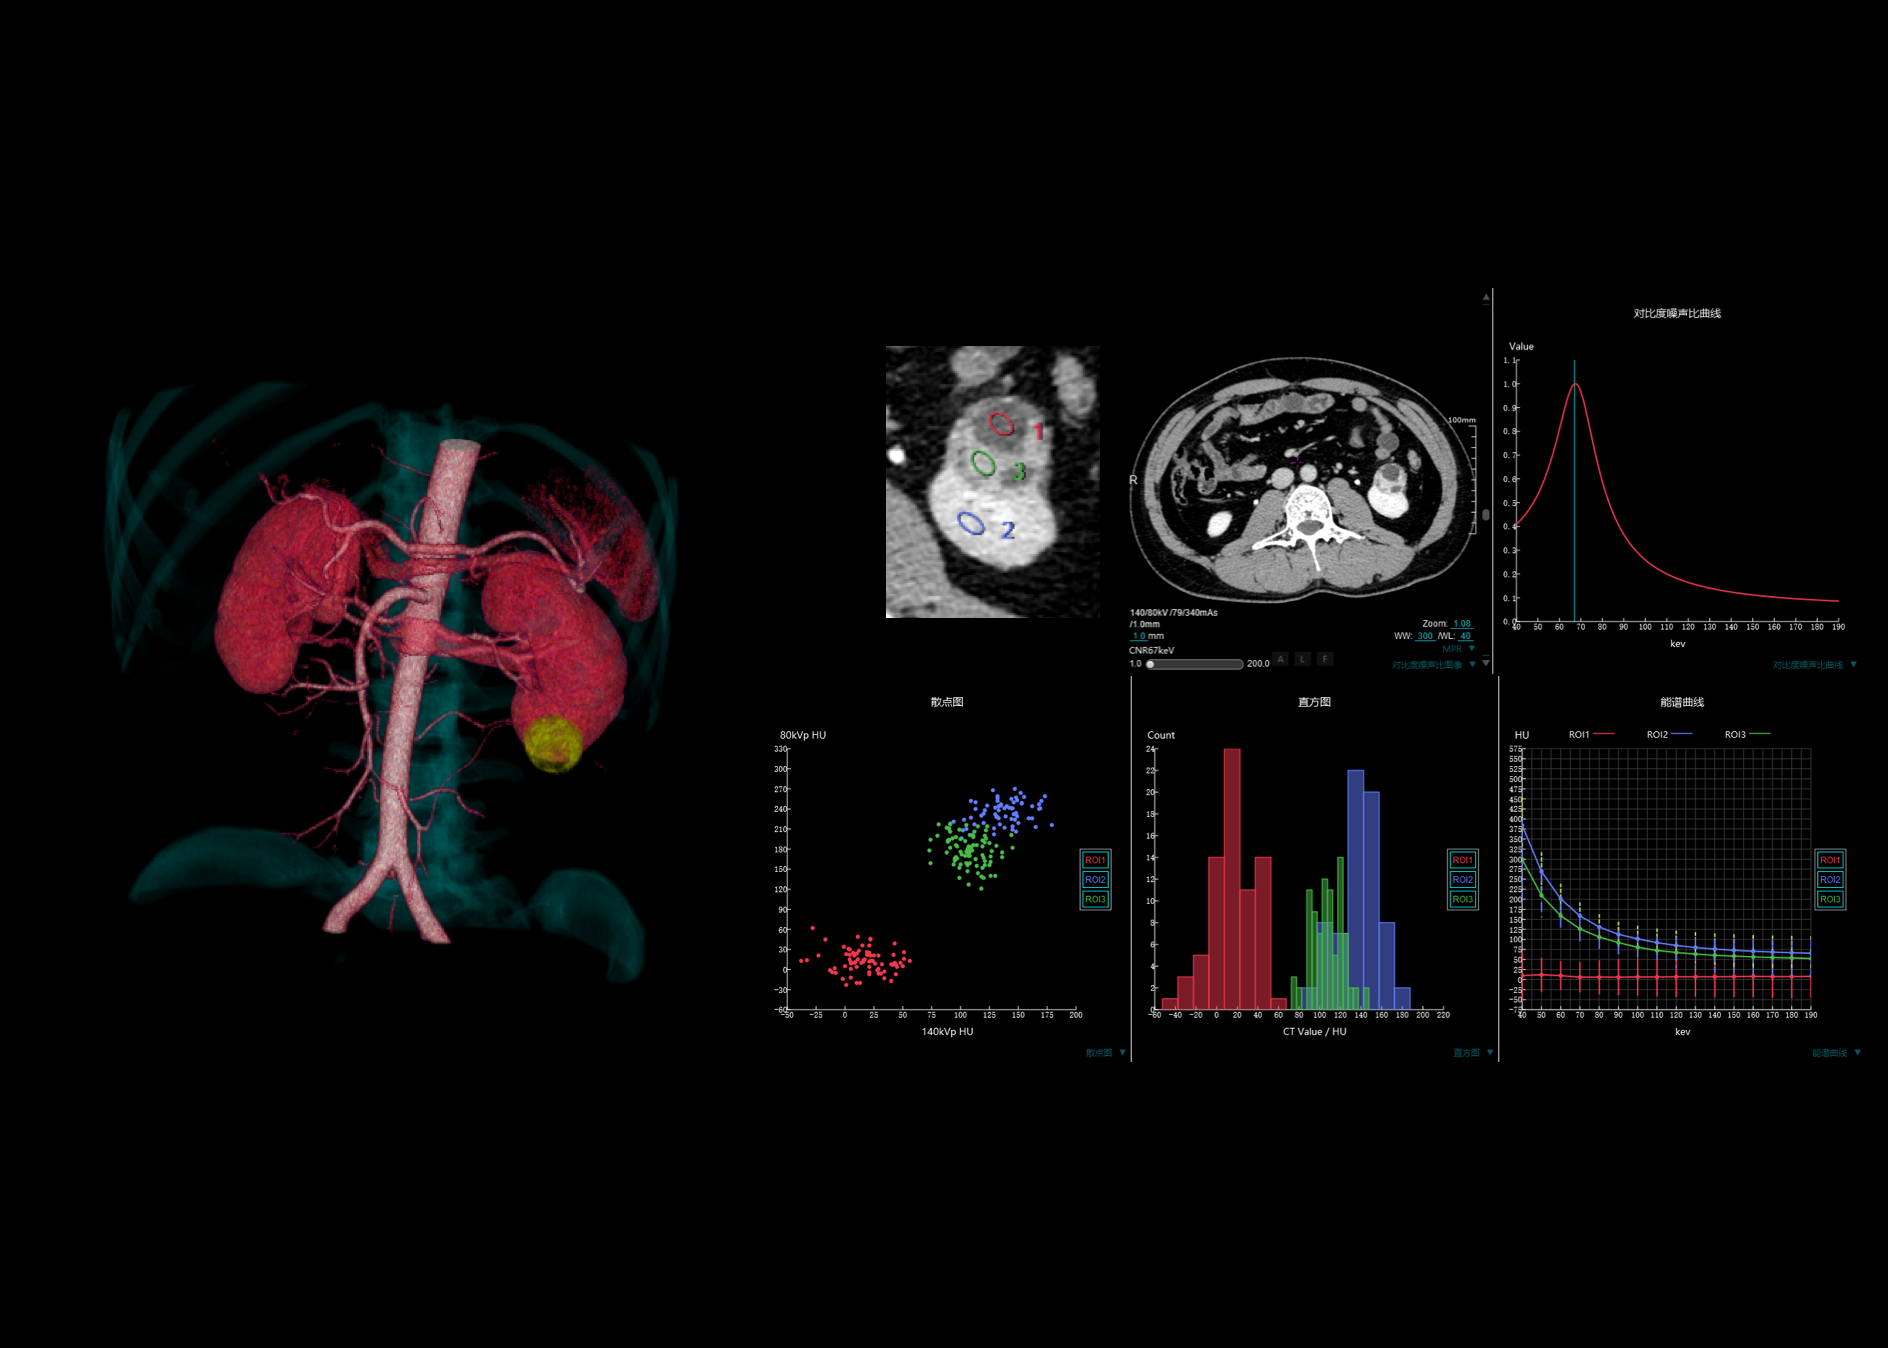

16厘米宽体能谱扫描,不动床轴扫覆盖单器官,获得组织中物质成分和能谱特征的定性及定量分析结果,为临床诊断提供更多可参考信息